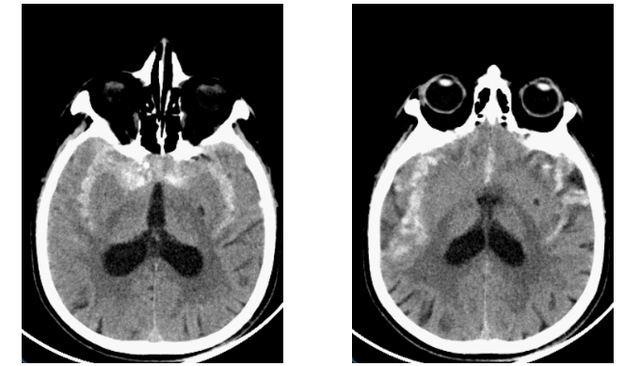

家住益阳沅江市的68岁赵叔,来医院前4小时突然出现剧烈头痛,休息后疼痛无好转,赵叔的儿子和女儿着急地带着赵叔去当地医院就诊,在当地医院完善头部CT检查后发现广泛蛛网膜下腔出血。

入院时急诊CT

以熊明主任医师为首的神经外科脑血管团队,在充分了解病情后,根据临床经验分析赵叔的病因是动脉瘤破裂出血的可能性最大,虽目前出血量不多,但如果动脉瘤再次破裂出血,随时可能有生命危险,建议进一步做脑血管造影(DSA)检查以便明确诊断,决定下一步手术治疗方案。